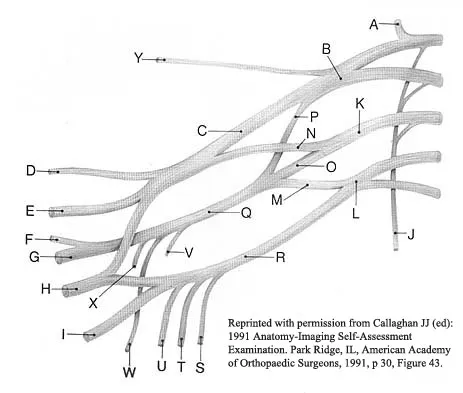

What structure is marked Q in the diagram of the brachial plexus shown in Figure 22?